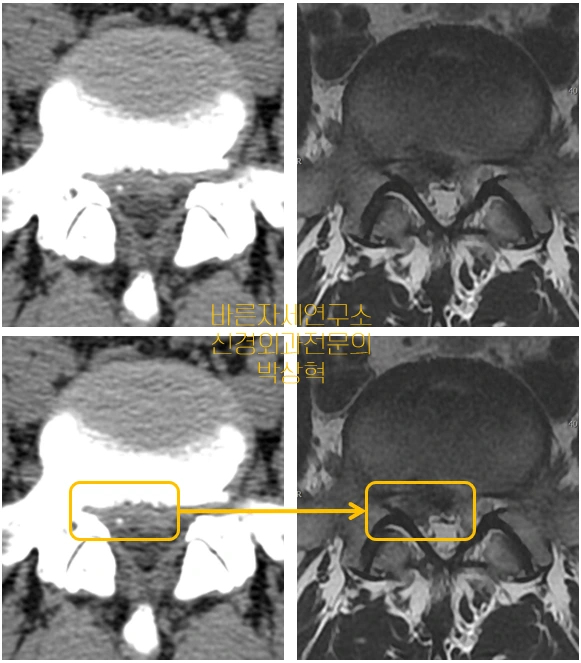

요통과 하지통이 심한 환자의 CT(좌) 와 MRI(우) 검사이다.

동일한 부위를 찍었기 때문에 보이는 그대로 비교해 보면 차이를 알 수 있다.

노란 사각형 안의 모습을 비교 해보면 좌측 CT 는 음영차이가 애매하여 경계가 불분명하고 흐릿하지만

우측 MRI 는 검은 색 (디스크) 과 흰색(신경) 의 경계가 선명하다.

즉 이 경우 [ 돌출된 디스크로 인해 통증이 심한 상태 ]에서

CT 는 병변이 뭉개지듯 흐릿하여 디스크 확진이 안되지만 MRI 에서는 파열된 디스크가 명확히 확진이 된다.